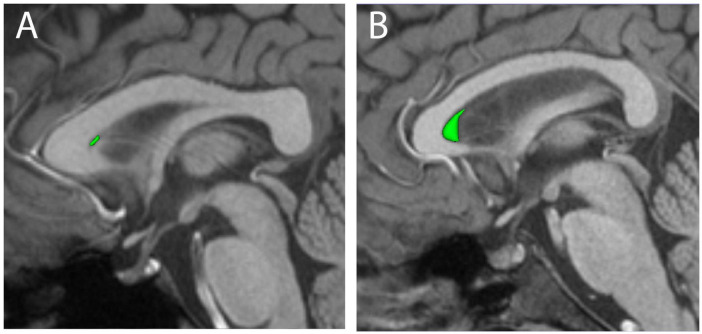

The cavum septum pellucidum (CSP) is a small cerebrospinal fluid-filled space found between the lateral ventricles of the forebrain that is often used as a biomarker for neurological disease and brain injury. The incidence of the CSP varies widely in different studies, with many reports finding that the CSP is frequently absent in healthy brains. Variables such as race, age and sex are typically not well-reported in CSP studies, presenting a challenge to understanding the normal distribution of the CSP in adult human brains. Moreover, the small size and frequently indistinct borders present a challenge for automated segmentation of the CSP. To address these issues, we developed a novel manual parcelation approach to volumetrically segment the CSP in high-resolution T1-weighted structural MRIs from male and female participants in the young adult dataset of the Human Connectome Project (HCP). We identified the CSP in 95.6% of subjects, compared to 57.1% when the automated segmentation approach was used on the same subjects. The CSP volume was significantly larger in male than female brains, both in terms of raw volume and volumes normalized for intracranial volume. To our knowledge, this study is the first to develop and validate a segmentation protocol for CSP volume, and to evaluate both the incidence and volume of the CSP in a representative population of young adults. Overall, these results provide a more accurate representation of the CSP in control populations, laying an improved foundation for its potential use as a biomarker for various disorders.